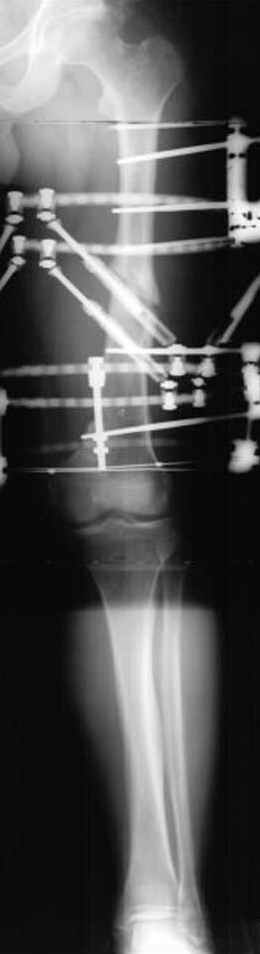

Несколько снимков из моей коллекции, чтобы разьяснить, почему мы до сих пор делаем различные варианты остеотомии.

На рисунке N1 предоперационный план лечения ложного сустава шейки бедра- линия ложного сустава, угол и направление введения импланта, клиновидная остеотомия в градусах и миллиметрах, второй снимок после коррекции, расчет, на сколько удлиняется конечность и размеры импланта;

N3 рисунок окончательный снимок, после операции моя рентгенограмма должен выглядеть примерно как эта картина. На N4 снимке клин перед удалением; N5 послеоперации 3 нед.; N6 окончательная рентгенограмма.

(доложен в Ст. Петербурге 2003 и в Москве 2004)

варус при проксимальном отделе 95 градусной пластиной.